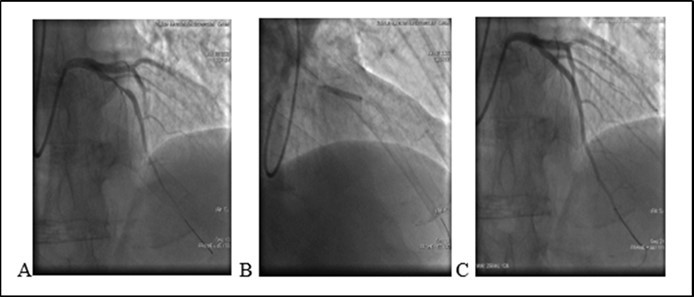

An 46-year old non-diabetic mail without history history of coronary artery disease 08.06.2020 was admitted to the cardiology department of Bokhua Memorial Cardiovascular Center ,with diagnoses of unstable angina (UA). Coronary angiography revealed 80% stenosis in medial segment of Left Anterior Descenting Artery (LAD). One bare metal stent was implanted in the stenotic segment (see Figure 1). The procedure was performed sucssesfully , without any procedure-related complications. After stent placement at hospital patient remaind simptom free. Heamodinamic parameters were stabile and he was discharged from hospital with appropriate prescription.

Figure 1.(08.06.2020) A. Medial stenosis in LAD. B. Stent implantation. C. Final result